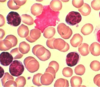

6

Q

A

erythroblasts - bone marrow